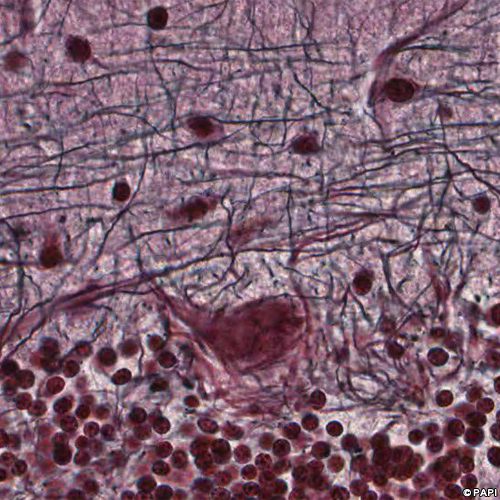

Red arrows indicate the Purkinje cells. Black arrows indicate the nuclei of the Bergmann glia which is the astrocyte in the Purkinje cell layer. Yellow arrows points the basket cell in the molecular layer.